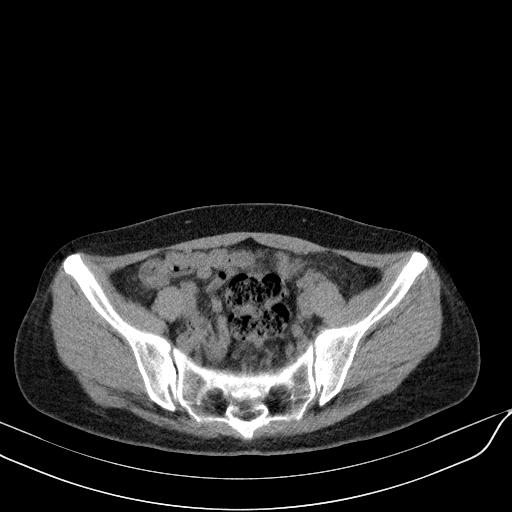

标题: CT23965:无外伤史,下腹痛 [打印本页]

标题: CT23965:无外伤史,下腹痛

肠道未准备,继续往下扫,乙状结肠占位不排除。建议钡灌或结肠镜检查。

乙状结肠占位不排除

肠道肿瘤,建议行钡剂灌肠检查。